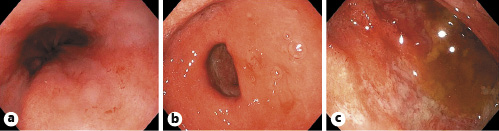

The patient is a 60-year-old female from the Dominican Republic who had lived in Spain for 10 years and was diagnosed with acquired thrombotic thrombocytopenic purpura with central nervous system involvement. Two months after the diagnosis she was admitted due to exacerbation of her illness with severe thrombocytopenia, in this case without neurologic symptoms. The evolution was slow, requiring high doses of corticosteroids, several sessions of plasma exchange, and rituximab to achieve remission of the hematological disease. After finishing plasma exchange and when the corticoids were being withdrawn, the patient began to experience persistent pyrosis, nausea, vomiting, and oral intolerance. Physical examination highlights epigastric tenderness. Blood tests showed hyponatremia (sodium 119 mEq/L, reference values 136-146) and leukocytosis with eosinophilia (20,790 leukocytes/µL with 18% of eosinophils). The patient presented euvolemic hyponatremia with criteria of SIADH (plasma osmolality 258 mOsm/kg, reference values 275-300; urine osmolality 588 mOsm/kg, reference values 50-1,200). Upper endoscopy was performed, and it showed esophageal, gastric, and duodenal mucosa with edema and erythema (Fig. 1). Moreover, there were superficial erosions and thickened folds in the duodenum. Gastric and duodenal biopsies were taken.

Fig. 1: Upper endoscopy image showing esophageal (a), gastric (b), and duodenal (c) mucosa with edema and erythema.